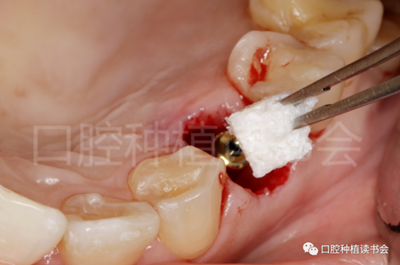

5.3.4 旋入覆蓋螺絲,在種植體與四周骨壁的間隙內(nèi)植入 Bio-Oss Collagen,植骨材料用生理鹽水濕潤后,用15#刀片分割為小塊分別植入,并用充填器壓實(shí)(圖17)。

圖17 后牙即刻種植植骨推薦使用骨膠原材料,有利于軟組織愈合。